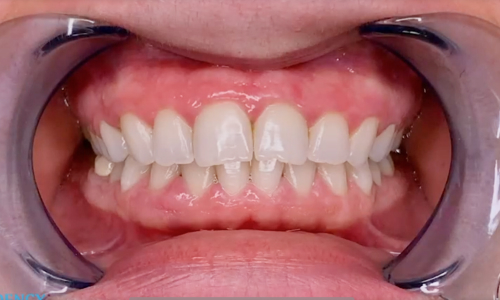

Процедура прошла успешно за один приём, без боли или дискомфорта. После отбеливания зубы пациента осветлились на несколько оттенков.

Primo-1.jpg